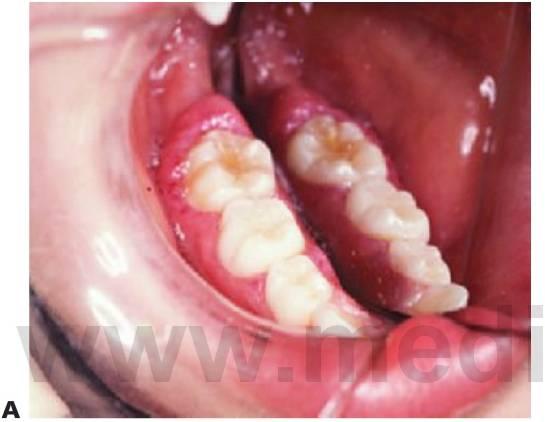

- Lesiones de mucho flujo: arteriales con fístulas arteriovenosas (fig. 8.11), que se presentan con dientes móviles y, en ocasiones, dolorosos así como pulsos palpables y auscultables, encías sangrantes y afectación ósea.

Diagnóstico

- Su presentación puede ser sutil, en forma de un sangrado prolongado en las encías después del cepillado, o bien, como un episodio hemorrágico muy intenso y único.

- Las lesiones vasculares suelen estar calientes al tacto, pero resultan difíciles de detectar si se llevan puestos los guantes.

- En las radiografías puede apreciarse un ensanchamiento del espacio periodontal y una trabeculación difusa anormal del hueso.

- Puede apreciarse igualmente un pulso o ruido en la auscultación de las lesiones de flujo alto.

- Los dientes pueden presentarse muy móviles y con movimientos pulsátiles.

- A medida que las lesiones se expanden, puede aparecer una asimetría facial.

- Se precisa la realización de una angiografía de sustracción digital (fig. 8.11B) para establecer el diagnóstico definitivo de los vasos nutricios y la distribución de la lesión.